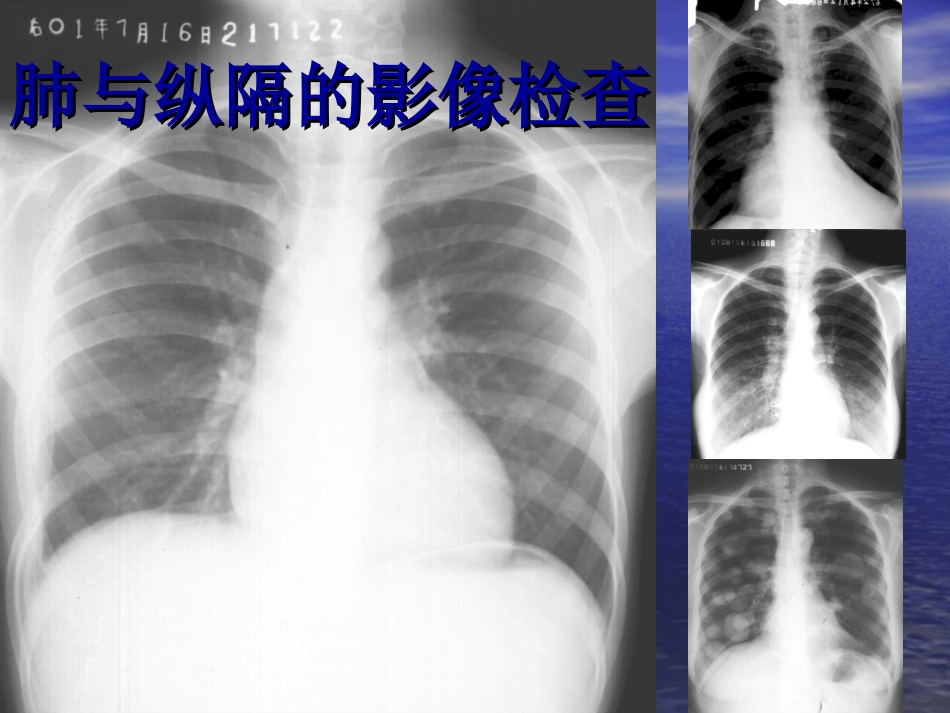

肺与纵隔的影像检查肺与纵隔的影像检查1.1.了解它的影像学检查方法。了解它的影像学检查方法。2.2.能对各个检查方法作出准能对各个检查方法作出准确的影像学诊断。确的影像学诊断。3.3.对于肺能做出它的分叶与对于肺能做出它的分叶与分段分段..并能结合并能结合CTCT做出真确判断。做出真确判断。4.4.能对常见的病例做出诊断。能对常见的病例做出诊断。肺与纵隔的检查技术肺与纵隔的检查技术•XX线检查:透视、拍片、体层、造影等线检查:透视、拍片、体层、造影等•CTCT:平扫、增强、螺旋:平扫、增强、螺旋•MRI:T1MRI:T1、、T2T2•超声成像:仅用于纵隔、心脏、胸膜疾病超声成像:仅用于纵隔、心脏、胸膜疾病胸部的正常胸部的正常XX线表现线表现•是胸腔内外各种组织结构的综合投影是胸腔内外各种组织结构的综合投影廓骨骼廓骨骼•肋骨肋骨•胸骨胸骨•锁骨锁骨•肩胛骨肩胛骨•胸椎胸椎肋骨和肋间隙常作为肋骨和肋间隙常作为胸部病变定胸部病变定位的标志位的标志•第第66前肋相当于前肋相当于9-109-10后后肋肋•肋软骨钙化顺序肋软骨钙化顺序11,,10-10-22•肋软骨钙化形式多样肋软骨钙化形式多样•变异:叉状肋、颈肋、肋变异:叉状肋、颈肋、肋骨融合骨融合胸膜胸膜•脏层与壁层胸膜间为潜在的胸膜腔脏层与壁层胸膜间为潜在的胸膜腔•斜裂胸膜:斜裂胸膜:第第4-54-5胸椎——前肋隔角后数胸椎——前肋隔角后数cmcm•水平裂:肺门向外下平第水平裂:肺门向外下平第66后肋后肋肺野示意图肺野示意图肺门肺门•正常肺门主要由肺正常肺门主要由肺动脉、肺静脉、支动脉、肺静脉、支气管等结构组成气管等结构组成•位于两肺中野内带位于两肺中野内带第第2-42-4前肋间前肋间•左侧比右侧高左侧比右侧高1-21-2cmcm肺门结构—肺门结构—22•右上肺静脉分支与右右上肺静脉分支与右下肺动脉干相交处为下肺动脉干相交处为肺门角肺门角•右下肺动脉干直径小右下肺动脉干直径小于于15mm15mm(小儿与气(小儿与气管直径相当)管直径相当)•左上肺静脉与左下肺左上肺静脉与左下肺动脉相交处为动脉相交处为肺门点肺门点肺纹理肺纹理•肺纹理主要由肺纹理主要由肺动脉分支形肺动脉分支形成成•观察肺纹理的变化观察肺纹理的变化主要依据印象、划主要依据印象、划线和对比等方法线和对比等方法肺叶肺段肺叶肺段•是肺脏的解剖结构是肺脏的解剖结构,,影像检查时只能大影像检查时只能大致判断其空间位置致判断其空间位置,,胸廓疾病时判断位胸廓疾病时判断位置有一定难度置有一定难度..肺叶肺叶--右上肺叶右上肺叶肺叶肺叶--右中叶右中叶肺叶肺叶--右下叶右下叶肺叶肺叶--左上叶左上叶肺叶肺叶--左下叶左下叶上叶肺段上叶肺段下叶肺段下叶肺段肺实质与肺间质肺实质与肺间质肺实质肺实质•具有气体交换功能的肺含气间隙及结构•主要是肺泡及肺泡壁肺间质肺间质•肺组织的支架结构•主要由血管、支气管及肺泡间隔的结缔组织构成气管气管•宽度宽度1.5—2cm1.5—2cm•长度长度11—13cm11—13cm•第第5-65-6胸椎水平分支胸椎水平分支•气管分叉角(隆突气管分叉角(隆突角)角)60—8560—85度度支气管支气管•左右侧支气管分支形式左右侧支气管分支形式与肺叶一致,与肺叶一致,了解双了解双侧支气管的分支有利于侧支气管的分支有利于判断肺部病变的解剖位判断肺部病变的解剖位置置•主主--叶叶--段段--亚段亚段--小小--细细--呼吸呼吸--肺泡管肺泡管--肺肺泡囊泡囊--肺泡(肺泡(3838级)级)纵隔纵隔•分区在判断纵隔病变的来源与性质上意义重大•六分区法六分区法食管前缘、气管心血管前缘胸骨角与第4胸锥体下缘连线纵隔分区纵隔分区纵隔的变化纵隔的变化•增宽增宽•变窄变窄•移位移位•局部包块局部包块•膈膈•内前侧高的圆顶状内前侧高的圆顶状•右侧较高右侧较高•一般位于第9-10后肋或第6前肋水平•呼吸幅度呼吸幅度1-31-3((3-3-66))cmcm•与胸壁相交与胸壁相交肋隔角肋隔角•与心脏相与心脏相交交心膈角心膈角膈(变异)膈(变异)•局限性膈膨升局限性膈膨升•波浪膈与梯状膈波浪膈与梯状膈正常胸部的正常胸部的MRIMRI表现表现•主要显示纵隔内和肺主要显示纵隔内和肺门部的血管、支...